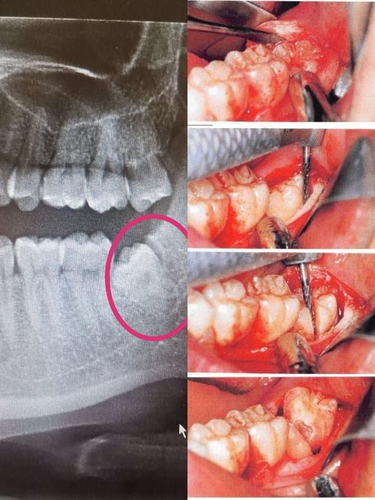

拔牙其实并不像大家想象中的那么难,但是拔牙如果不能合理化,那么是会产生一定的不良影响,伤到神经的情况也是有可能发生的。同时还会导致出血、肿胀、疼痛等不好的反应,有些甚至破坏到了牙神经,前面说的还好解决,但对于牙神经的伤害后果是非常可怕的:

首先在伤到神经以后会让牙齿的营养丢失,也没有办法再进行供应,其它牙齿就会受到影响,从而出现各种各样的问题。

其次如果有这样的后果出现,会使牙齿更脆,变的不如之前那么坚硬。牙神经在杀死后,牙齿寿命会相对缩短。在牙神经杀死以后,会根管治疗还有根管充填,把它补起来。这样在以后就永远不会感觉痛了,这也是一种好事。